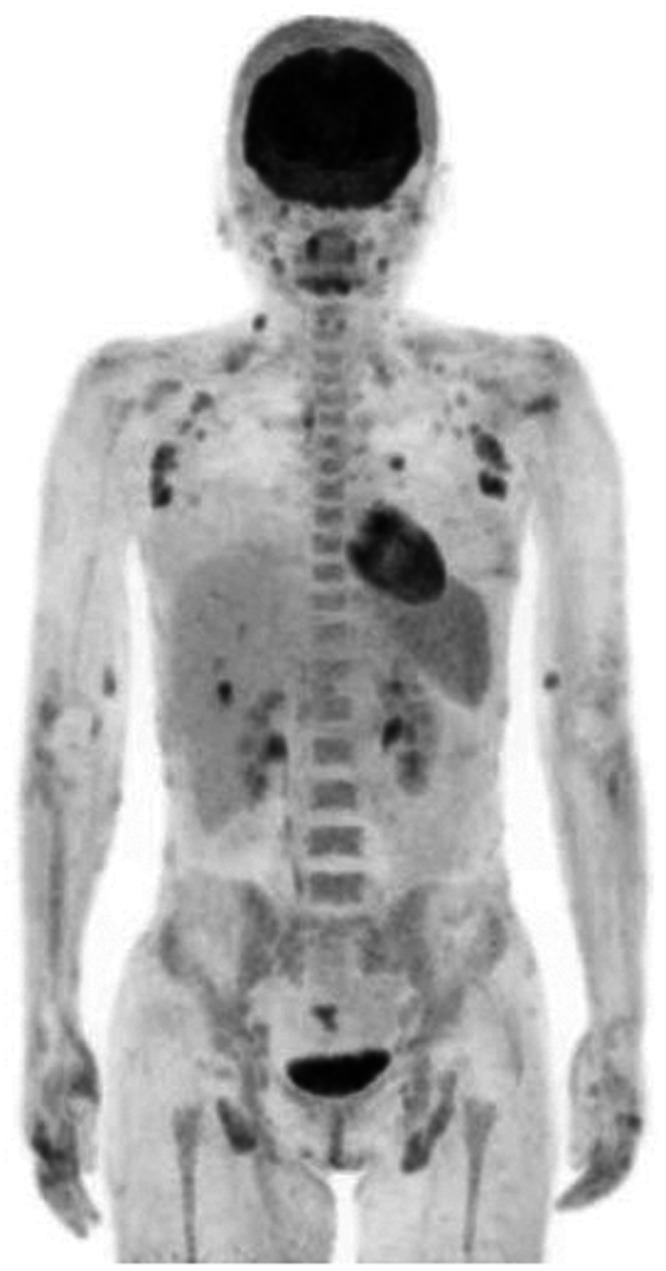

A 29-year-old woman with chronic, prolonged pustular psoriasis was admitted to our hospital because of high-grade fever and a systemic skin rash. General examination revealed a whole-body skin rash and superficial lymphadenopathy. Peripheral blood examination showed unclassified cells positive for CD3, CD4, and T-cell receptor αβ, and negative for CD20 and CD56. Soon after administration, she developed acute respiratory failure and required artificial ventilation. Bronchoalveolar lavage fluid showed increased numbers of eosinophils and abnormal lymphocytes of the same phenotype in peripheral blood and skin. She was diagnosed with eosinophilic pneumonia, and her respiratory failure was improved by corticosteroid therapy. Based on the histological findings of skin, lymph node, and bone marrow biopsies, a diagnosis of peripheral T-cell lymphoma not otherwise specified (PTCL-NOS), with positivity for CC chemokine receptor 4 was made. She received chemotherapy followed by allogeneic stem cell transplantation, which resulted in complete remission of her PTCL-NOS. She remained alive and disease-free 6 years later. This is the first reported case of PTCL-NOS developing during the clinical course of pustular psoriasis. The clinical manifestations of PTCL-NOS are complex, but an accurate diagnosis and appropriate therapy may produce a good clinical outcome in patients with PTCL-NOS.

一位 29 岁的女性患有慢性、迁延性脓疱性银屑病,因高热和全身性皮疹入住我院。全身检查发现全身皮疹和浅表淋巴结病。外周血检查显示未分类细胞 CD3、CD4 和 T 细胞受体 αβ 阳性,CD20 和 CD56 阴性。用药后不久,她出现急性呼吸衰竭,需要人工通气。支气管肺泡灌洗液显示外周血和皮肤中嗜酸性粒细胞和异常淋巴细胞数量增加,表型相同。她被诊断为嗜酸性粒细胞性肺炎,皮质类固醇治疗改善了她的呼吸衰竭。根据皮肤、淋巴结和骨髓活检的组织学发现,诊断为未分类的外周 T 细胞淋巴瘤(PTCL-NOS),CC 趋化因子受体 4 阳性。她接受了化疗和异基因造血干细胞移植,PTCL-NOS 完全缓解。6 年后,她仍然存活且无疾病。这是首例脓疱性银屑病病程中发生 PTCL-NOS 的报道。PTCL-NOS 的临床表现复杂,但准确的诊断和适当的治疗可能会给 PTCL-NOS 患者带来良好的临床结局。